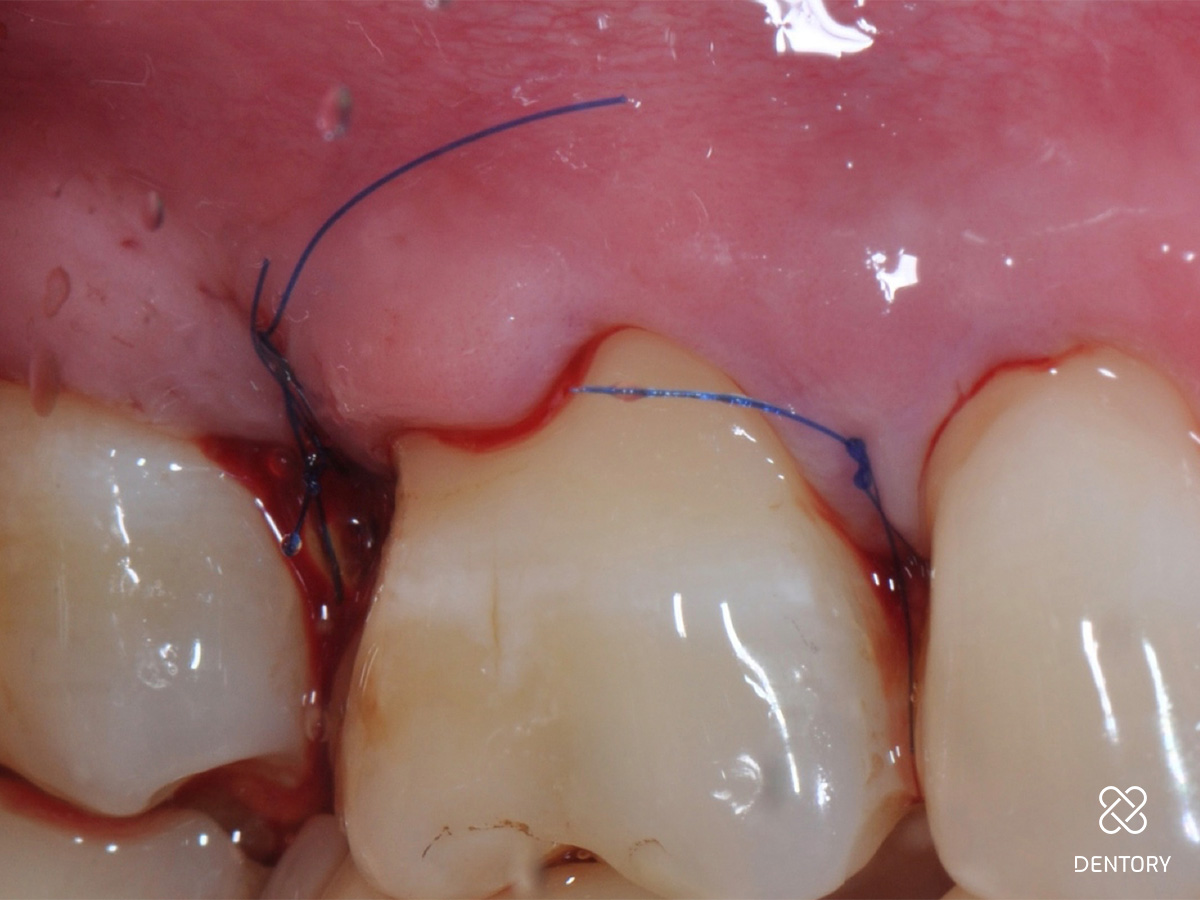

Abbildung 10

Primärer Wundverschluss: Ein primärer Wundverschluß ist eine unbedingte Voraussetzung für eine erfolgreiche Regeneration. Mit einer zweischichtigen Nahttechnik werden die beiden Lappen Stoß-auf-Stoß adaptiert.